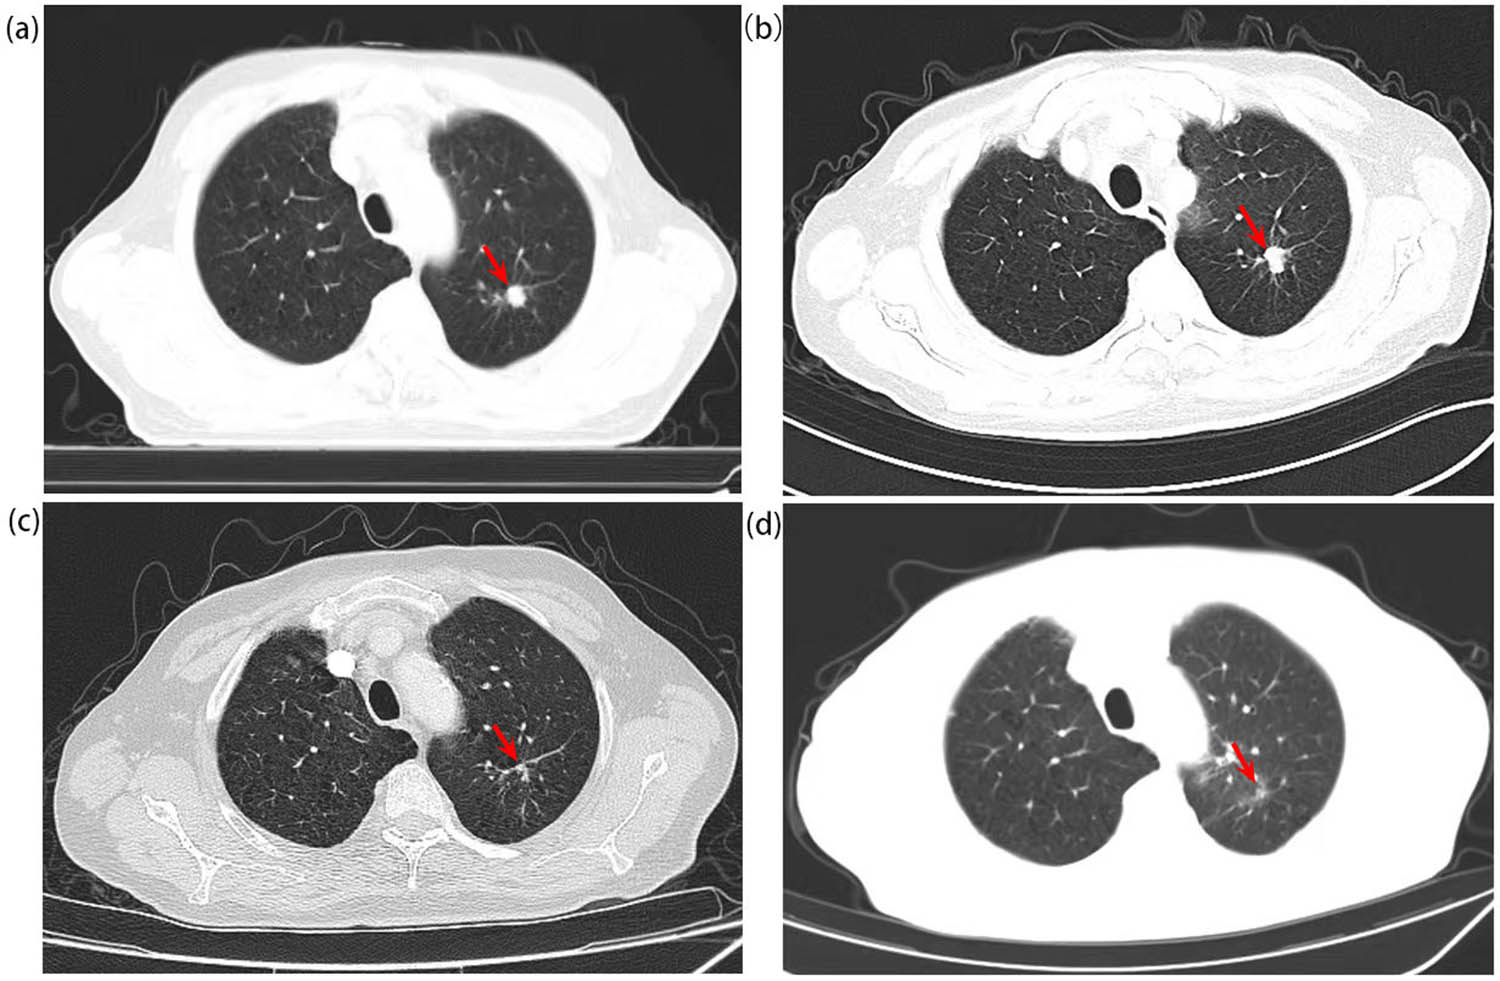

In August 2020, a 64-year-old male presented with haematuria and dysuresia for 2 weeks, both computerized tomography (CT) and ultrasound of the abdomen showed a tumour in the bladder triangle area (38 mm × 23 mm, Figure 1a and b) and another one in the prostate (Figure 1c and d). Chest CT found a nodule located in the left lung (11 mm × 12 mm, Figure 2a). The serum PSA was elevated (total PSA was 11.3 μg/L, free PSA was 1.01 μg/L). The patient had a history of smoking for 40 years, about 2 packs/day; drinking for 30 years, 150 g/day, and had quit smoking and drinking for 1 year, since he was diagnosed with hypertension 1 year ago. Besides, he underwent lower limb vein exfoliation surgery 10 years ago and repaired his left groin hernia 5 years ago.

The CT scan of the chest shows the lung carcinoma: (a) shows a nodular hyperdense shadow seen in the posterior segment of the left upper lobe of the lung with medium contrast in August 2020 (with a size about 11 mm × 12 mm). (b) Shows the lesion before chemotherapy plus immunotherapy against PD-1. (c) Shows that the lesion was significantly reduced after two cycles of chemotherapy plus immunotherapy against PD-1. (d) Shows that the lesion almost disappeared after radiotherapy.

Later, the patient underwent radical cystoprostatectomy through laparoscopy and cutaneous terminal ureterostomy in the Department of Urology on January 4, 2021. Postoperative pathological results were consistent with the previous ones: namely, prostate adenocarcinoma, Gleason score 4 + 3 = 7, immunohistochemistry showed AMACR (+), PSMA (+), HCK (−), and P63 (−); bladder urothelial carcinoma (high level), immunohistochemistry was: PCK (+), GATA-3 (+), P63 (+), CK7 (+), CK5/6 (strong +), CD44 (partial weak +), and CK20 (stove +). After the radical surgery, regular endocrine therapy began every 3 months and PSA was kept below the normal value. But soon, venous thrombosis (incomplete embolism) was found in his shallow vein of the lower limbs, and anticoagulation therapy with low molecular heparin was given. As he refused surgery and radiotherapy for the lung lesion at that time, from March 20, 2021 to June 6, 2021, he received 4 cycles of pemetrexed and carboplatin plus pembrolizumab, the evaluation was partial response (PR) after second and fourth cycles (Figure 2b and c). According to the strong requirements of the patient, bevacizumab was added in the fifth cycle on July 2, 2021. But right after that myocardial infarction occurred in July 2021 and he was in poor physical condition, so he was treated with cardiovascular diseases and all treatments against cancers were terminated. Then, from January 3, 2022 to January 14, 2022, he received radiation for his left lung lesion (50 Gy/10 fractions). After that, the lung lesion almost disappeared (Figure 2d) and he underwent regular follow up thereafter. On April 15, 2022, he received “Bentall” surgery due to the aneurysm of the aortic root. Maintenance treatment of pembrolizumab monotherapy was started and still ongoing since April 2022, and he is in good condition now and PSA is still kept below the normal value (total PSA detected in September 2022 was 0.008 μg/L, free PSA<0.01 μg/L), no cancer recurrence or metastasis has been detected nowadays, overall survival (OS) was more than 26 months.